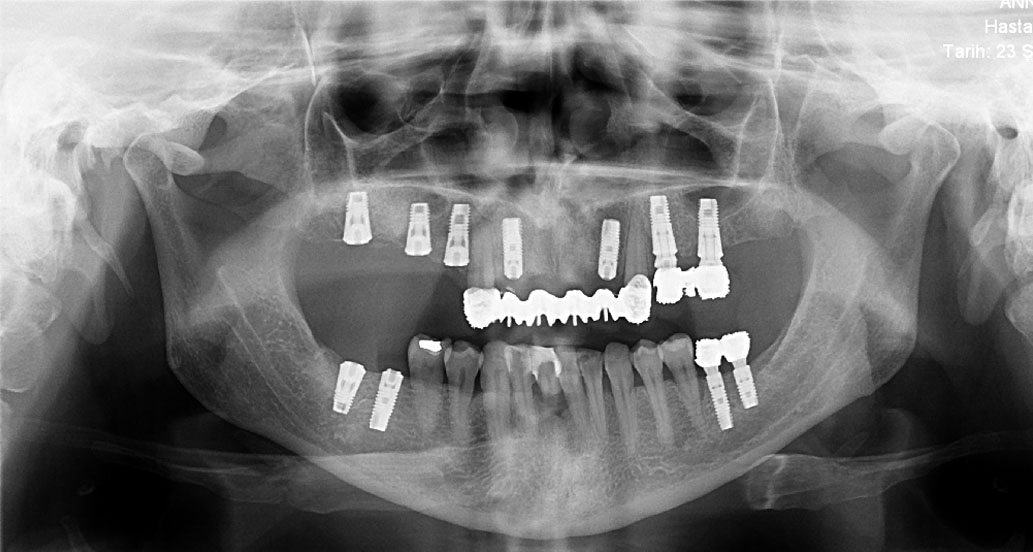

Ýmplant

İmplant (Diş kökü olmayan bölgelere uygulanan suni kökler)